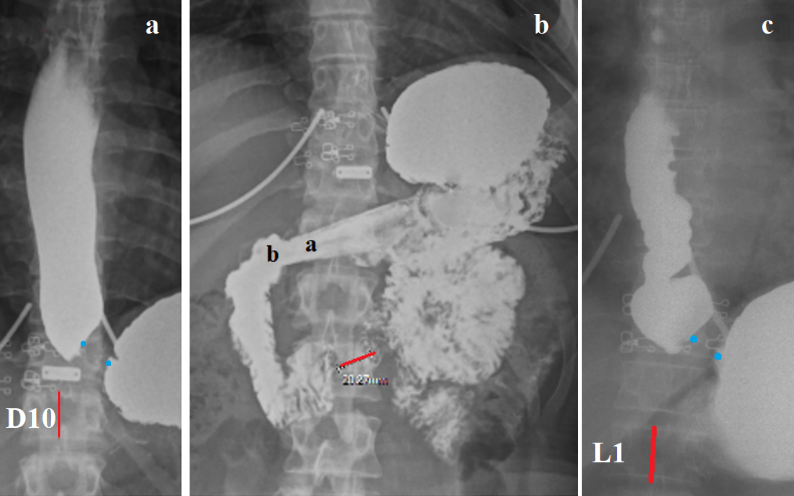

Based on the study by Shafik et al. [3], which demonstrated that high gastric pressure causes contraction of both the UES and LES, I was the first to use radiographic imaging of the esophagus and LES under maximal gastric pressure, which allowed us to measure the length of the functional portion of the LES. In addition, the simultaneous contraction of the UAS and LES caused swallowed barium to become trapped between the contracted sphincters, which allowed us to measure the width of the esophagus, detect functional sphincters, esophageal stenosis, and changes in its contour [7]. This method can be part of an X-ray examination of the esophagus, stomach, and duodenum or as an independent study if the suspicion of GERD was not confirmed after endoscopy. The patient, lying on the X-ray table, continuously drinks barium suspension through a straw from a jar standing at his head. When the barium runs out (200-250 ml), he immediately raises his straightened legs. At this moment, an x-ray is taken from the pharynx to the body of the stomach. It should be noted that a delay between the last swallow and the raising of the legs may necessitate a repeat examination because the x-ray will only show traces of barium in the esophagus since during this time all the contrast agents will penetrate the stomach. After the first radiograph, the subject gets up, but after 5 minutes he lies down again on the X-ray table. A second radiograph is taken at rest to determine the completeness of barium evacuation into the stomach and the possibility of free reflux (Figure 2).

Figure 2. Radiographs of patients with GERD were taken at the maximum gastric pressure. (a). Since the height of D10 in adults is approximately 2 cm (red line), the length of the contracted LES between the two blue dots is 1 cm, which is significantly less than the minimum normal limit (3.2 cm) [7]. It is combined with a sharp dilation of the esophagus – 2.3 cm instead of 1.7 cm. (b). At 5 minutes, the straightened walls of rigid anatomy gastritis (a) are visible. The duodenal bulb (d) has a star shape, indicating duodenitis. The contraction of the Ochsner sphincter (red line, 2 cm long) confirms the presence of hydrochloric acid hypersecretion. (c). Since the height of L1 is 2.2 cm, the length of the contracted LES between the two blue dots is 1 cm, which is significantly less than the minimum normal limit (3.2 cm). The width of the ampulla above the LES is 3.1 cm. The contours of the esophagus indicate an inflammatory process.

In 59 of 60 patients with at least one symptom characteristic of GERD, the diagnosis was confirmed by the method described above. Among them, there were two patients in whom pH monitoring excluded GERD, since the acid exposure time (AET) was < 4%. One patient had no pain syndrome. The study was ordered due to suspicion of non-esophageal symptoms of GERD, which was excluded [7]. The observations shown in Figure 2 convincingly indicate that GERD is the tip of the iceberg, which occurs due to hypersecretion of hydrochloric acid and is therefore always accompanied by pathology of the stomach, duodenum and biliary tract. These diseases leave their mark on the clinical picture. Recently, against the background of PPI treatment, ulcerative lesions of the stomach and duodenum are very rare. Histological studies are not performed in the absence of erosion. The presence of acid in the esophagus with a pH of less than 4 for less than 1.5 hours is mistakenly recognized as normal [1]. For these reasons, many supposedly functional diseases have been invented, because of which patients with hypersecretion of hydrochloric acid do not receive timely pathogenetic treatment [11-13].